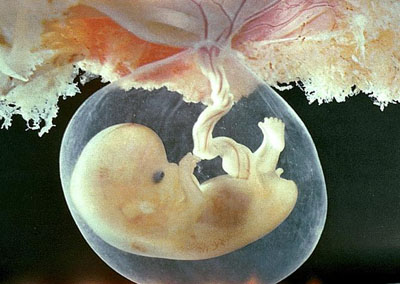

Даний період поки що прийнято вважати ембріональним. Ваш малюк на даному терміні більше схожий на інопланетного гостя, ніж на маленького чоловічка. Його головка набагато більше тулуба і нахилена вперед, ближче до грудей. Саме тільце нагадує «хвостик». Але не варто лякатися, адже так колись виглядав кожен з нас, а «хвостик» зникне зовсім скоро, ближче до 10-му тижні.

Незважаючи на те, що вигляд малюка ще далекий від людського обличия, в його організмі вже протікає чимало найважливіших для подальшого життя процесів. Головний з них - сердечко повністю сформувалося і почало битися! Друге важливе досягнення пов'язане з повним закриттям нервової трубки, що надзвичайно важливо для психічного розвитку малюка.

У цей період відбувається формування передньої стінки живота, тонкого кишечника, кори надниркових залоз, стравоходу і трахеї, також активно розвивається мозок плоду. Крім того, ручки і ніжки крихти стали довшими, а на їх кінцях утворилися розщеплення, які в недалекому майбутньому перевтіляться в пальчики. На обличчі позначилися очі, повіки, ротик і навіть ніздрі. Починається формування мови. У 6 тижнів ваш майбутній малюк вже підріс до 8 мм.

на вагітність 6-7 тижнів фото можна помилуватися на майбутнього малюка, правда, зараз його можна порівняти з космічним прибульцем - у плода навіть можна спостерігати хвіст. який атрофується до 10-му тижні.

Триває формування організму дитини: з'являються тонка кишка і грудина, коркова частина надниркових залоз. Активно формуються передня стінка живота, трахея і стравохід. Розвиток мозку також йде семимильними кроками. Звичайним явищем виявляється зникнення правої пупкової вени. Довжина плоду становить приблизно 7,9 мм.

В 7 тижнів вагітності розмір плода

становить близько 2 см в довжину, голова має вже майже 1 см в діаметрі. Головний мозок продовжує розвиватися, підрозділяючись на 5 частин, в подальшому з них сформуються відділи. Передній відділ мозку поступово стає органом зору, утворюється сітківка очей, створюються нервові зв'язки.